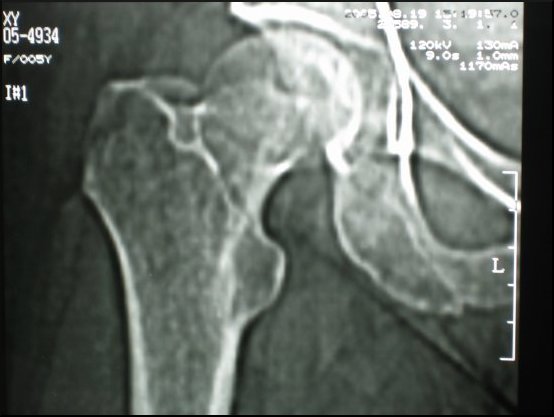

Dobierając skład chemiczny i strukturę materiału kompozytowego, z którego wykonujemy modele przeznaczone do szkoleń, główny nacisk położyliśmy na dokładne odtworzenie właściwości naturalnej kości. W tym celu poddaliśmy kość różnorodnym badaniom. Tą samą technikę zastosowaliśmy badając modele z materiałów kompozytowych.